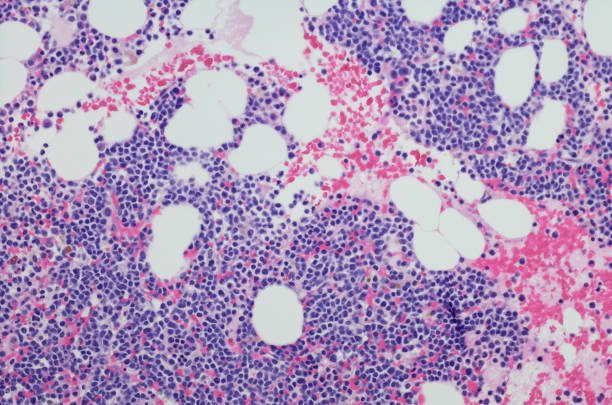

The U.S. Food and Drug Administration (FDA) has approved daratumumab and hyaluronidase-fihj (Darzalex Faspro) in combination with bortezomib, lenalidomide, and dexamethasone (VRd) for adults with newly diagnosed multiple myeloma who are ineligible for autologous stem cell transplant. Approval was based on the Phase III CEPHEUS trial, which demonstrated significantly higher minimal residual disease (MRD) negativity […]